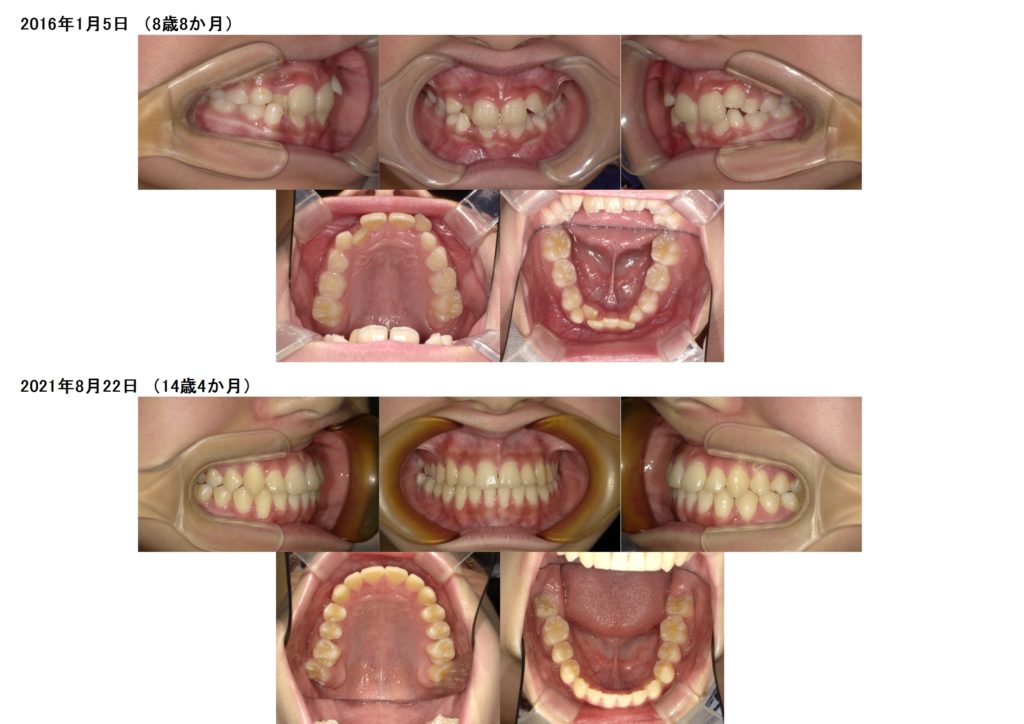

↑初診時の写真と、装置を入れ、永久歯の生えるスペースを確保した写真の比較になります☆

上の写真で分かる所は、上の2番目の歯が中に入っているのと、下の歯も1本完全に中に入っていますね。

このまま永久歯が全部生えるのを待っていると、将来キレイな歯並びにするのに歯を抜く可能性が出てきます。

まだお子様の成長期の間にその子の永久歯の生えるスペースを確保します。

こんな感じでキレイな歯並び、噛み合わせになりました。

このように早めに治療を開始すると、将来抜歯せずにキレイな歯並びになります☺